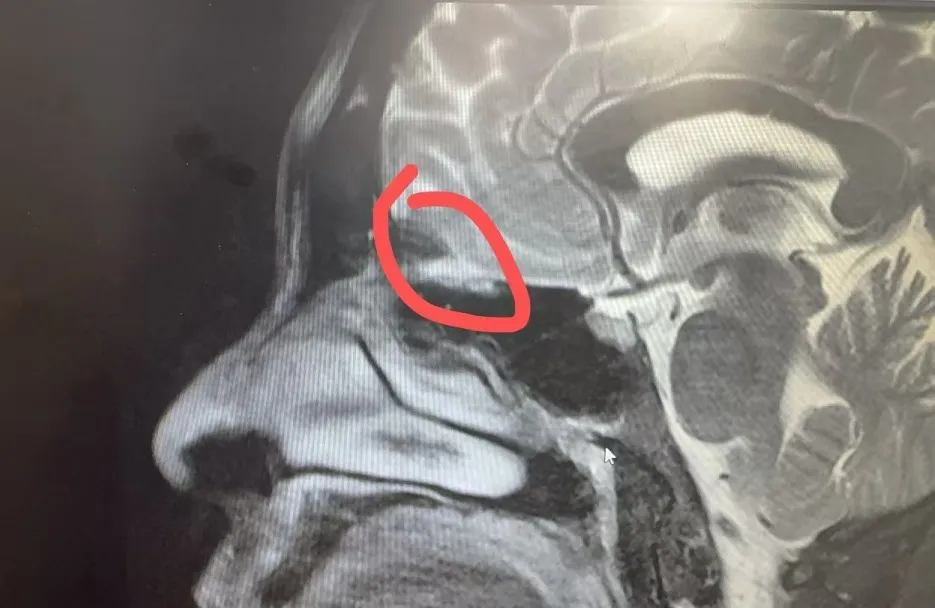

經(jīng)過充分的術(shù)前準(zhǔn)備,耳鼻咽喉頭頸外科陸訓(xùn)彪主任帶領(lǐng)團(tuán)隊為患者實施了經(jīng)鼻內(nèi)鏡腦脊液鼻漏修補(bǔ)術(shù),術(shù)中發(fā)現(xiàn)嗅裂頂部存在約2mm大小的白色略透明的膜狀膨出物,考慮腦膜腦膨出。術(shù)中用中鼻甲粘膜移植覆蓋瘺口,并特別注意保護(hù)周圍神經(jīng)和血管,精心處理好瘺口周圍組織,力求最大程度減少復(fù)發(fā)風(fēng)險。經(jīng)過團(tuán)隊的共同努力,手術(shù)圓滿成功,術(shù)中僅出血約20ml。